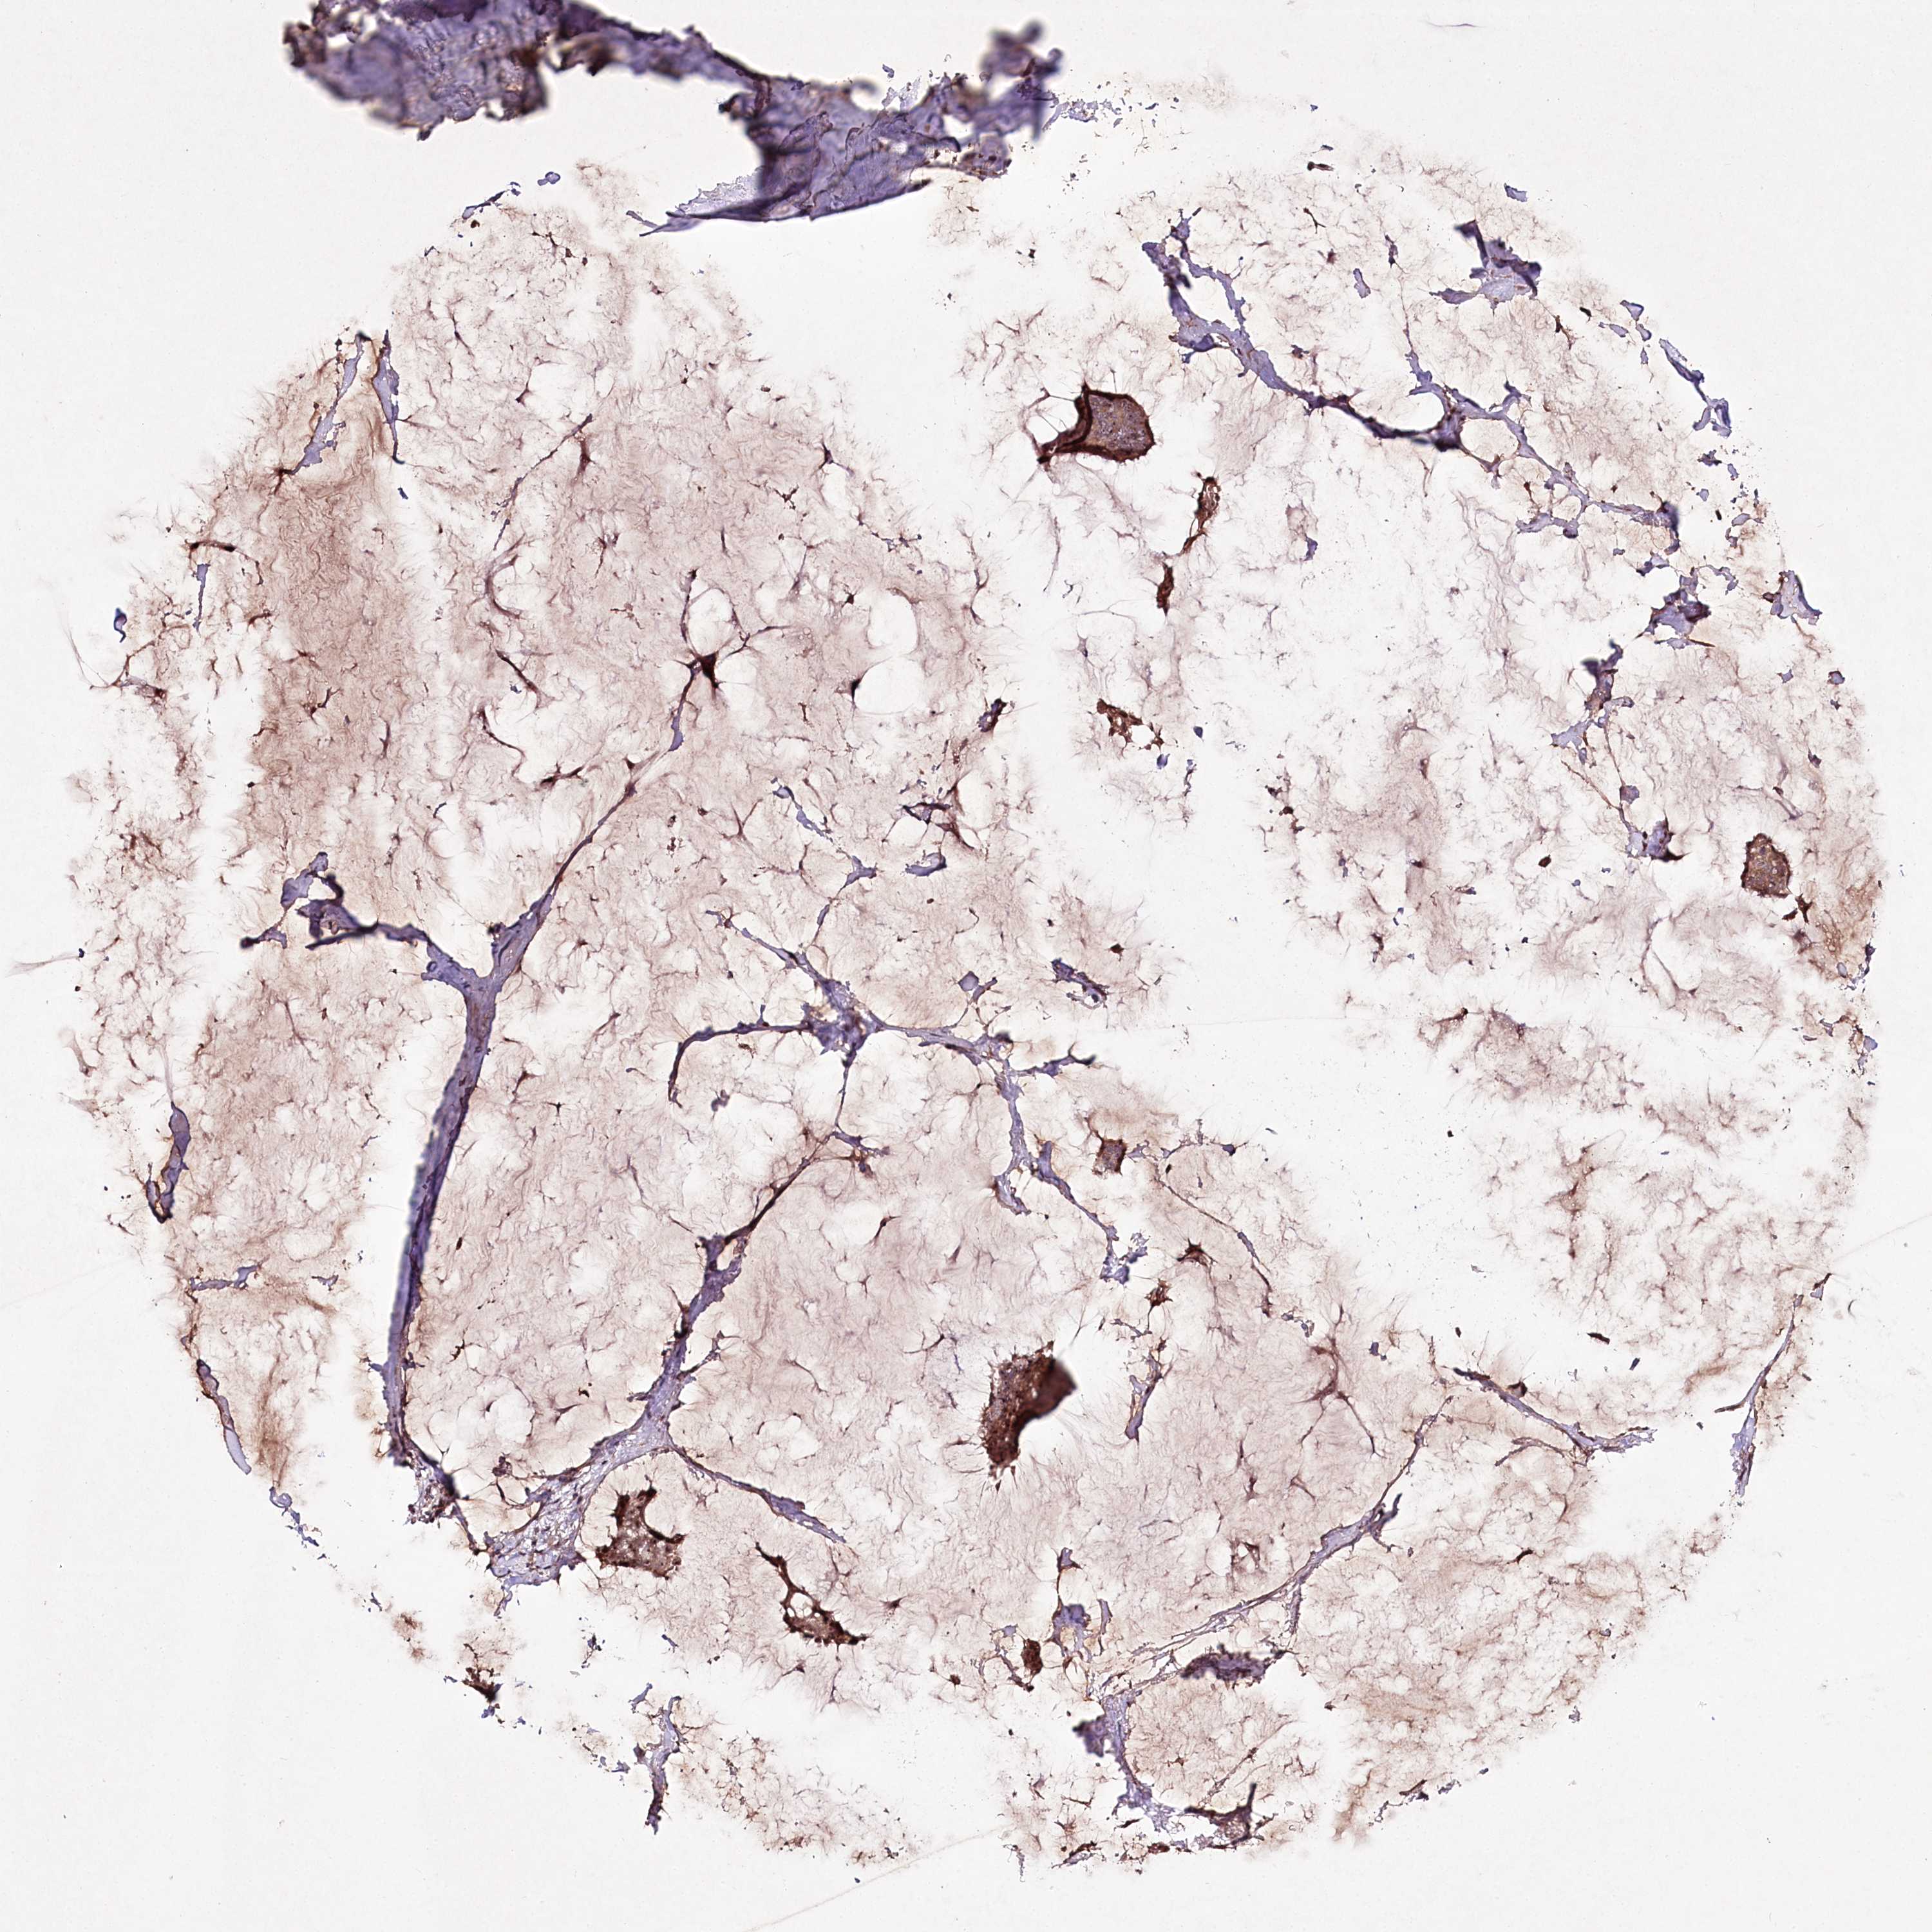

CANCER BREAST CANCER Show tissue menu

BRCA TCGA BRCA VALIDATION PROTEIN EXPRESSION